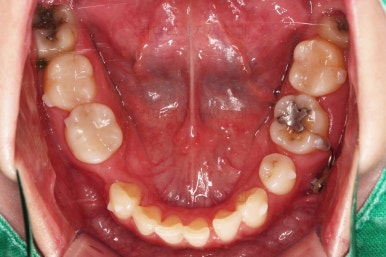

초진 시 입안의 모습인데요.

왜 그런지 비밀이 풀리는 것 같죠?

윗니는 한 쪽이 치아 2개가 결손이면서 유치가 하나 남아있고요.

아랫니는 한 쪽은 1개, 반대편은 2개 치아가 결손이었습니다.

도합 5개의 치아가 결손이었는데요.

결손 위치의 갯수가 위아래 좌우 다 달라서 중앙선이 맞을래야 맞을 수가 없는 상황이었죠.

결손치아 주위 치아들은 쓰러지고 비틀어져 있어서 장기적으로 좋지 못한 상황이었고요.

좀 더 디테일하게 윗니 작은 앞니 1개가 왜소치아라서 치아 크기도 맞지 않은 상황이었습니다.